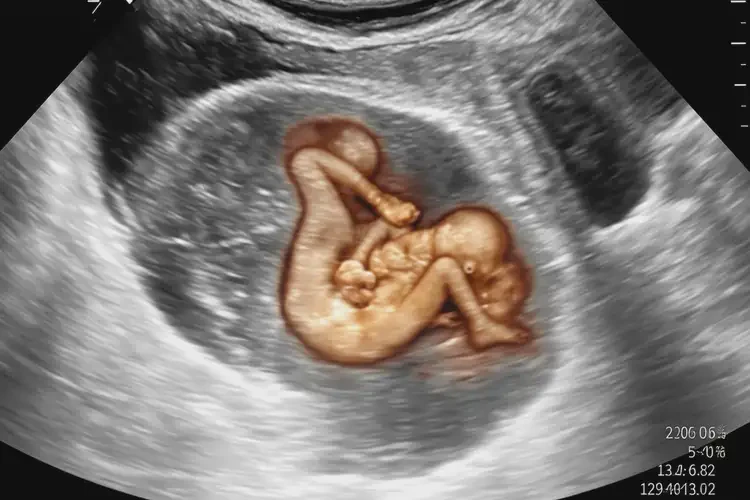

孕19周1天胎心165正常嗎(圖1)

孕19周1天胎心165正常嗎(圖2)

孕19周1天胎心165正常嗎(圖3) 孕19周1天胎心165正常嗎(圖4)